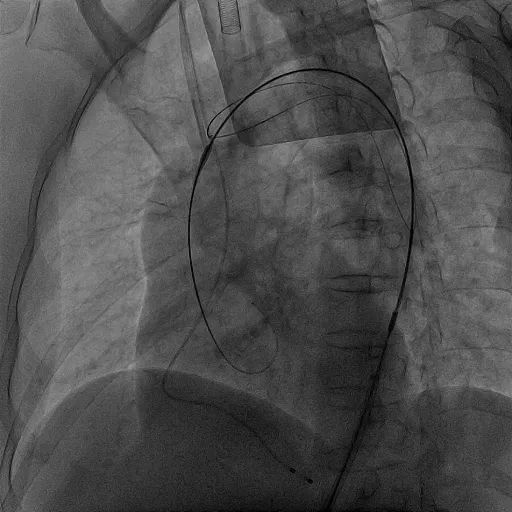

TriGUARD3™定位

TriGUARD3™完成释放